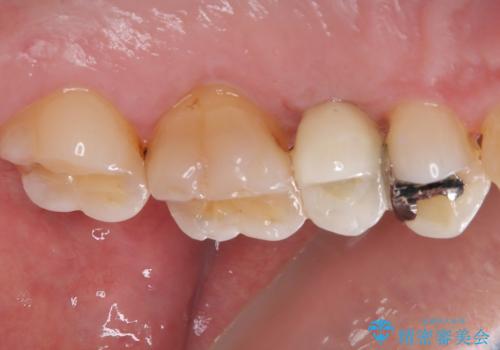

- むし歯で抜歯したまま放置していたとのことで来院された患者様です。

仕事が忙しいことと、外科手術が怖いとのことで歯科医院を避けていたものの、当院の1DAYインプラント治療を見て、重い腰を上げて来院されたとのことでした。

事前に仮歯を用意し、インプラント埋入時に仮歯を装着し、その後歯肉の治りを待って速やかにオールセラミッククラウンにて補綴治療を行うこととしました。